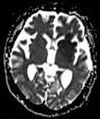

Examples of T1-weighted, T2-weighted and PD-weighted MRI scans

Each tissue returns to its equilibrium state after excitation by the independent relaxation processes of T1 (spin-lattice; that is, magnetization in the same direction as the static magnetic field) and T2 (spin-spin; transverse to the static magnetic field).

To create a T1-weighted image, magnetization is allowed to recover before measuring the MR signal by changing the repetition time (TR). This image weighting is useful for assessing the cerebral cortex, identifying fatty tissue, characterizing focal liver lesions, and in general, obtaining morphological information, as well as for post-contrast imaging.

To create a T2-weighted image, magnetization is allowed to decay before measuring the MR signal by changing the echo time (TE). This image weighting is useful for detecting edema and inflammation, revealing white matter lesions, and assessing zonal anatomy in the prostate and uterus.

T1 and T2 values are dependent on the chemical environment of the sample; hence their utility in MRI. Soft tissue and muscle tissue relax at different rates, yielding the image contrast in a typical scan.

The standard display of MR images is to represent fluid characteristics in black-and-white images, where different tissues turn out as follows: